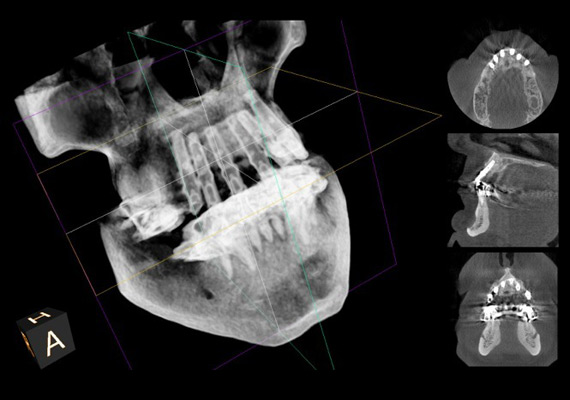

La 3D Radiology: an Essential Technology

3D radiology has significant diagnostic advantages and enables extraordinary surgical planning and precision.

For implantology, it helps determine bone graft requirements and the optimal choice of implants. It provides a complete view of the sinuses and the inferior alveolar nerve.

During wisdom tooth extractions, this technology helps to accurately identify the trajectory of the nerve that gives feeling to the chin and the lip and minimizes the risk of prolonged numbness following the extractions.